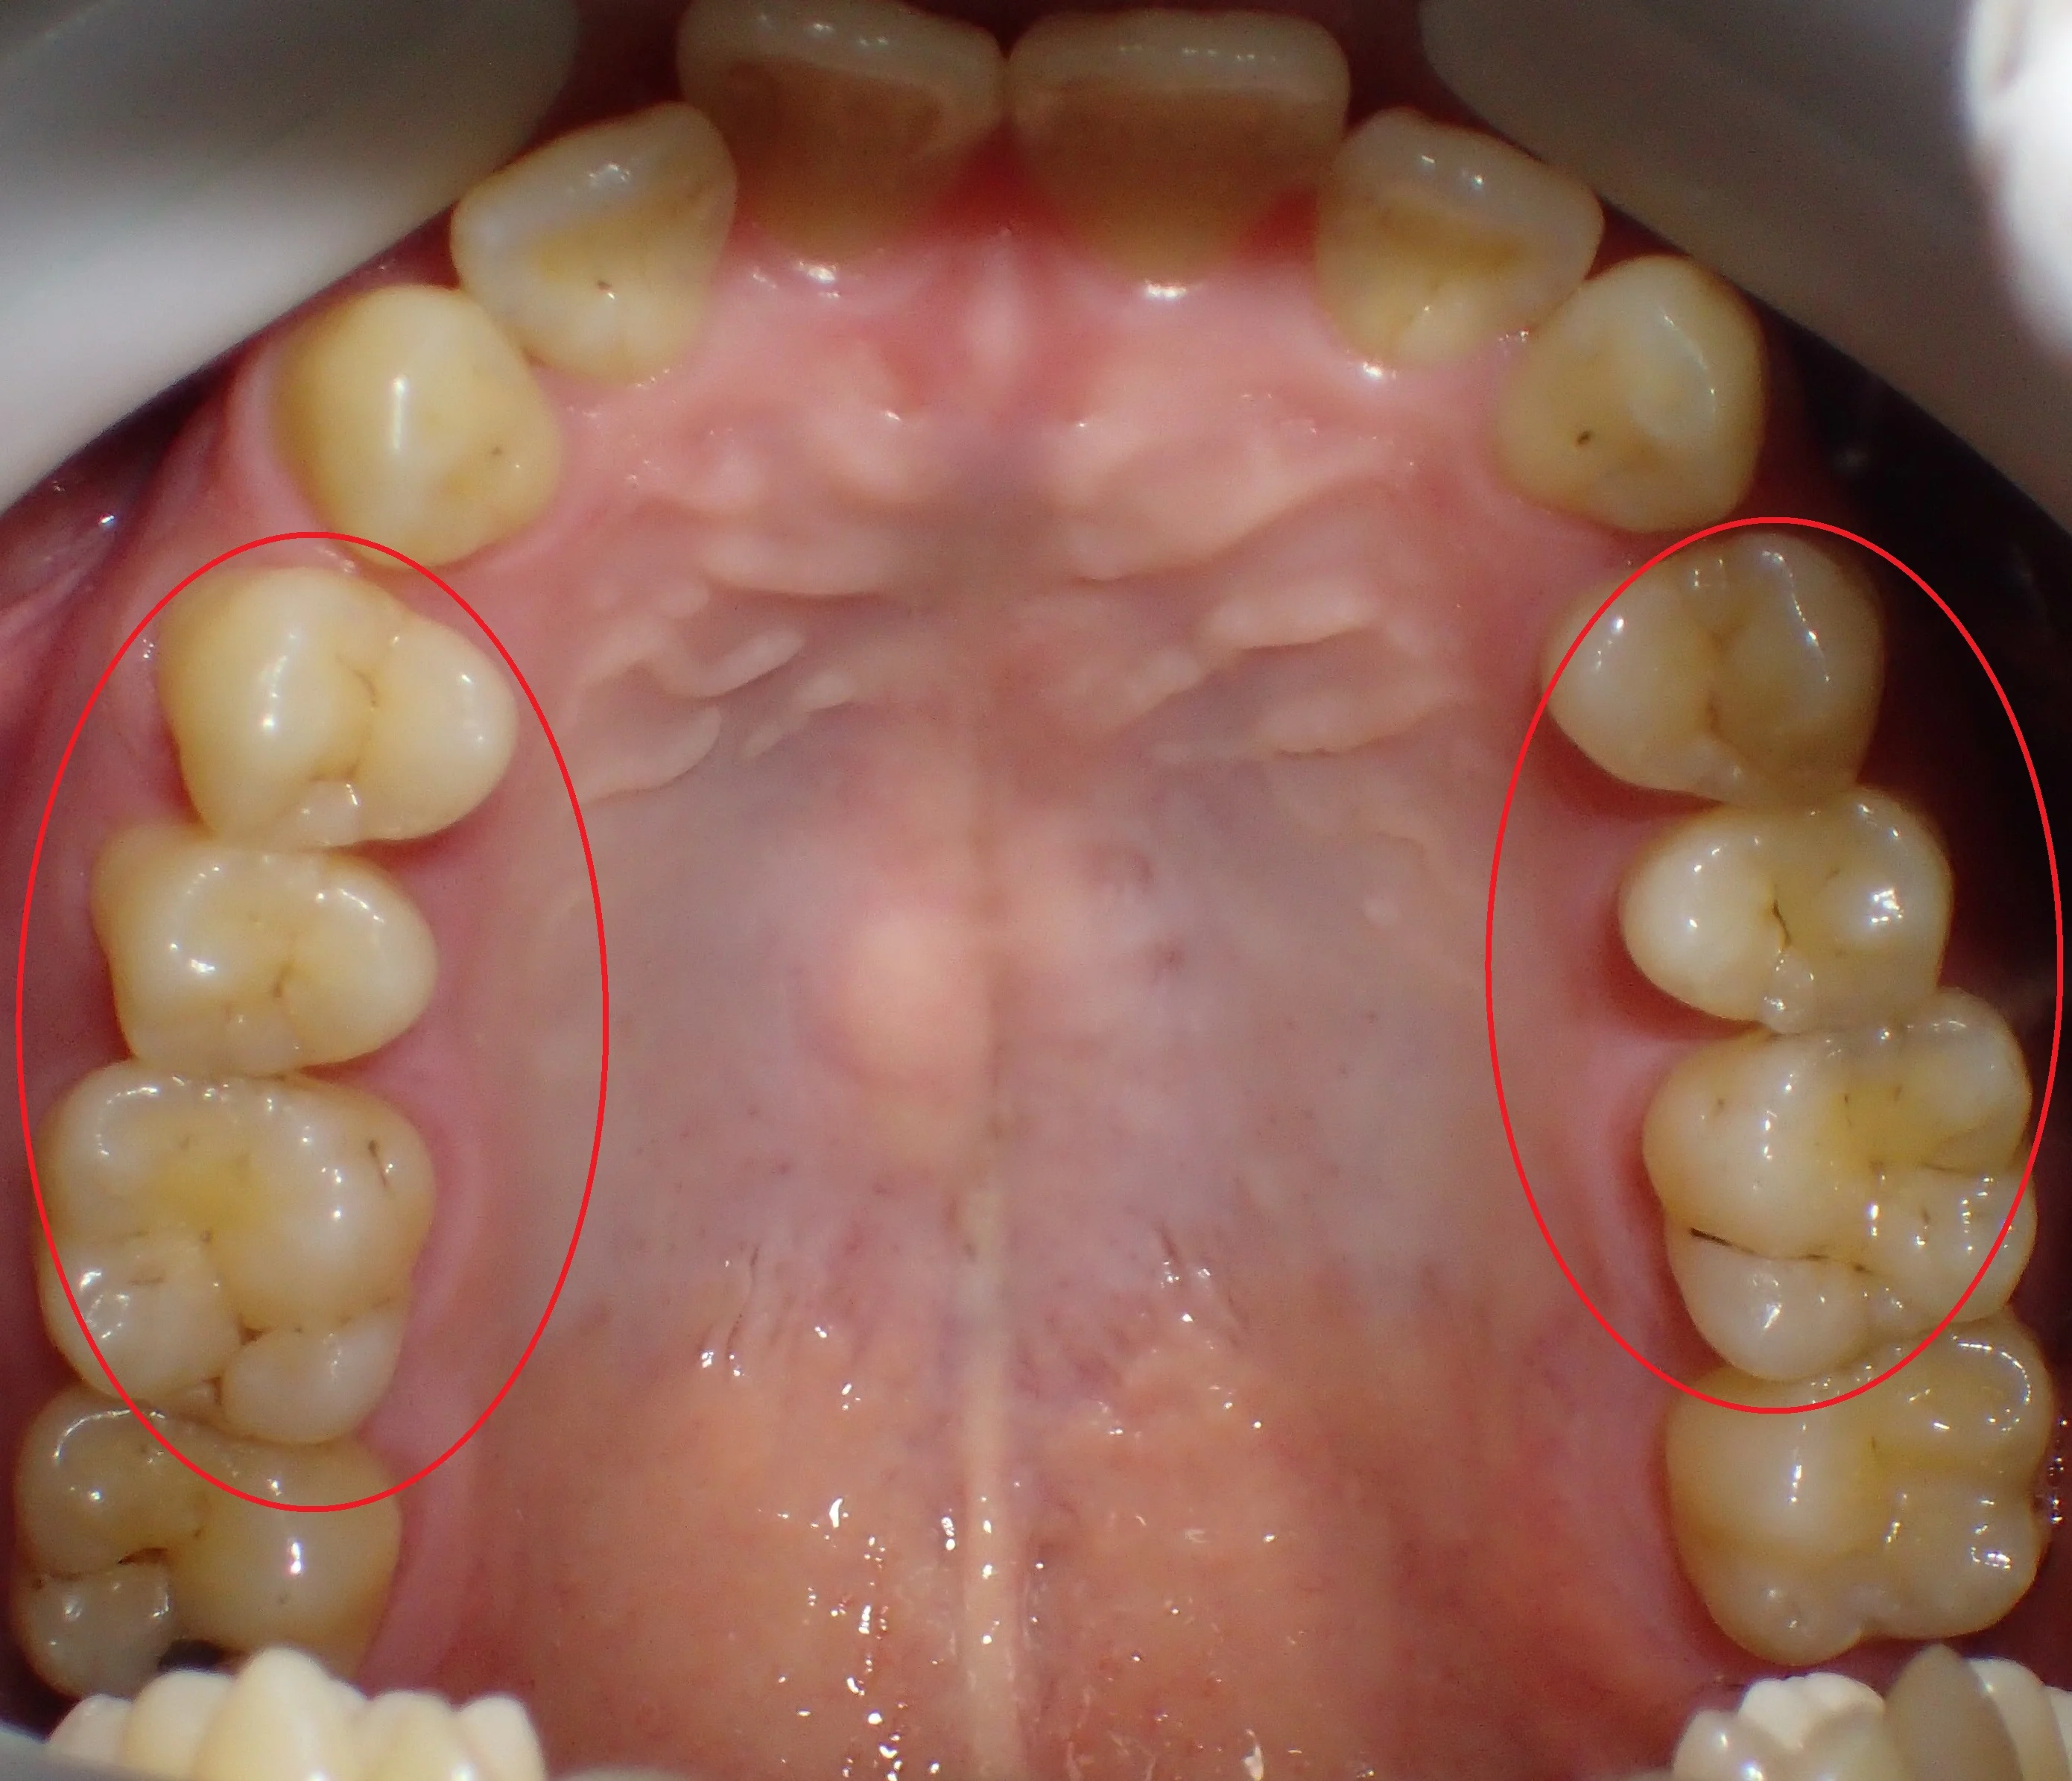

まだ坂寄歯科医院には全顎的にダイレクトボンディングで治療した症例がありませんので、前の医院にて治療を完了された方の写真を載せたいと思います。

どこを治療したかわかりますか?

答えは下の方に書いておきますので、スクロールしてください。

治療した箇所は、

・右上4,5,6

・左上4,5,6

・右下5,6

・左下5

でした!

治療した部位は全て元々詰めていたメタルインレーが再び虫歯になってしまった状態でした。

幸いあまり大きくは削られてはいなかったので、全てをダイレクトボンディングで治療することが出来ました。

ステイニングを行って、歯の溝の部分に色を付けると歯に立体感が出るので、急激に天然の歯っぽくなりますよね!

もう少しステイニングを弱めにしてほしいとの要望があり、他の箇所は控えめなステイニングにしました。

全ての治療を終え、患者さん本人には非常に喜んでもらえました。